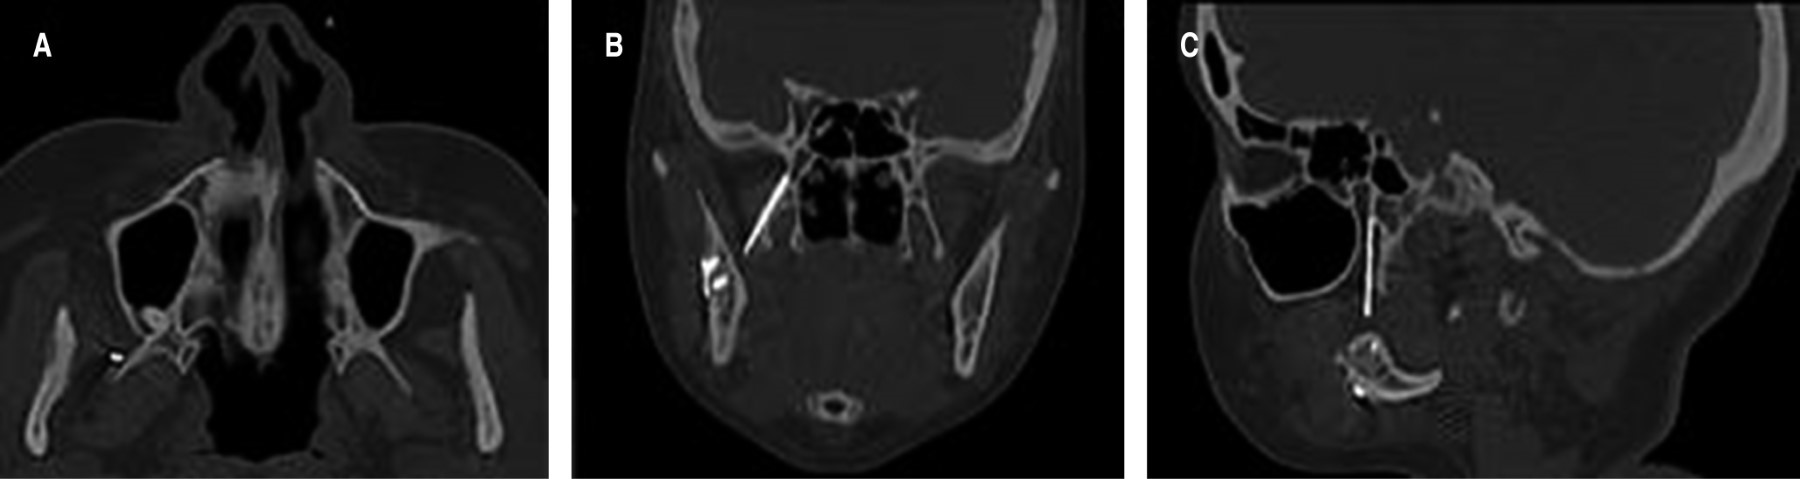

Dentro de los hallazgos imagenológicos se encontró imagen hiperdensa de forma fusiforme, de densidad similar al metal, de una longitud de 2.6 cm y un diámetro de 2 mm, esta misma se localizaba en la FP derecha, al correlacionar con el antecedente quirúrgico este CE era compatible con un fragmento de una broca percutánea del sistema 2.0; también se observan imágenes hiperdensas compatibles con una miniplaca de osteosíntesis con cuatro tornillos en ángulo mandibular, así como un área hipodensa correspondiente al trazo de fractura en proceso de cicatrización (Figuras 1 y 2).

Se realizó el retiro del CE mediante el fluoroscopio en sala de operaciones con un abordaje mínimamente invasivo en fondo de vestíbulo, pudiendo encontrar y remover exitosamente el CE de la FP derecha (Figuras 4 y 5). Posteriormente, se trató a la paciente mediante una férula miorrelajante, acompañada de fisioterapia por un lapso de cuatro meses, logrando así la recuperación de la apertura bucal, 35 milímetros aproximadamente (Figura 6). Es importante mencionar que entre el CE y los tejidos blandos circundantes se formó un área de tejido fibroso, la cual estaba condicionando la limitación de la apertura bucal. Se tomaron radiografías de control, las cuales evidenciaron la correcta consolidación de la fractura de ángulo derecho (Figura 7). Finalmente, la paciente fue transferida a ortodoncia para realizarse el tratamiento ortoquirúrgico de la maloclusión clase III.